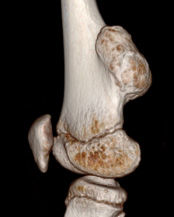

Dev Hücreli Kemik Tümörü

Kemiğin selim-agresif tümörü olarak kabul edilir. Genç erişkinde osteolitik karakterde kemik tümörüdür. Uzun kemiklerin ekleme yakın uç kısmından çıkabilir. Hastalar tümör bölgesinde devamlı ve giderek artan inatçı bir ağrı ve şişlik ile başvururlar.Sadece küretaj yapılan hastalarda yüksek lokal nüks yanında akciğer metastazı yapma potansiyeli olduğundan lokal agresif tümör olarak kabul edilir. Ama bu metastazlar ölümcül değildir.Diz eklemi en sık tutulan bölgedir. Diğer sık tutulan bölge el bileğidir. Kemik korteksini harap ederek yumuşak dokulara yayılım gösterebilir. Tanı için biyopsi şarttır. Brown tümörü ile ayırıcı tanısı yapılmalıdır. Tanı esnasında akciğer tomografisi çekilmelidir.

Tedavide genişletilmiş küretaj ve adjuvan ajanlarla kalan tümör hücreleri öldürülmeye çalışılır. Adjuvan ajan olarak; sıvı azot, alkol, fenol, argon koter, kriyoterapi, yüksek hızlı burr ve sementleme (kemik çimentosu) uygulanır. Eklemin tutulduğu vakalarda eklem feda edilir,protez veya artrodez uygulanabilir. Rezeksiyonun zor olduğu olgularda denosumab kullanılması önerilmektedir.Hastaların lokal nüks ihtimaline karşı 10 yıl süre ile takibi yapılmalıdır.